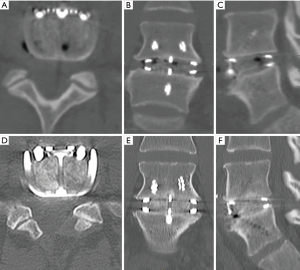

A 37-year-old female presented with low back pain on a background history of multiple microdiscectomy surgeries performed at L4/5 over a 9-month period. Figure 2 reveals significant disc height loss, Modic type 2 endplate changes, and a positive bone scan at the L4/5 articulation. Conservative therapies were exhausted over 6 months. An L4/5 ALIF was performed (Figure 2), using a Redmond (A-Spine ASIA, Taiwan) 3-screw integral fixation ALIF construct packed with allograft bone and DBF. The patient was closely followed-up over a 3-month time period. Early osseointegration is detected at 3 months with significant reduction of her discogenic pain.

Both cases we report on had SCCO2 allograft bone and DBF mixed with approximately 2 mL of the patient’s blood (via a sterile sample provided by anaesthetic staff at time of graft preparation). This mixture was then transferred into the ALIF cages, and given its consistency, was easily packed tightly. Post operatively, CT images (Figures 1,3) showed graft materials in the desired position with minimal spreading and transposition of bone fibres.

DBF graft, when used in conjunction with allograft DBM, showed to have fusion on post-operative CT scans (as shown in both cases) at as early as 3.5 months post-operatively (Figure 1A,B), with a solid construct by the 12-month mark (Figure 1C,D). Both cases outlined above had only SCCO2 treated allograft bone (Allovance® Crunch; Australian Biotechnologies, Sydney, Australia) mixed with osteoinductive DBF (Allovance Fibre Mat; Australian Biotechnologies, Sydney, Australia) and autologous blood. In selected patients with low risk of failure to fuse, the use of DBF with SCCO2 allograft can reduce the requirement of rhBMP, hence mitigating the risk of side-effects associated with its use.